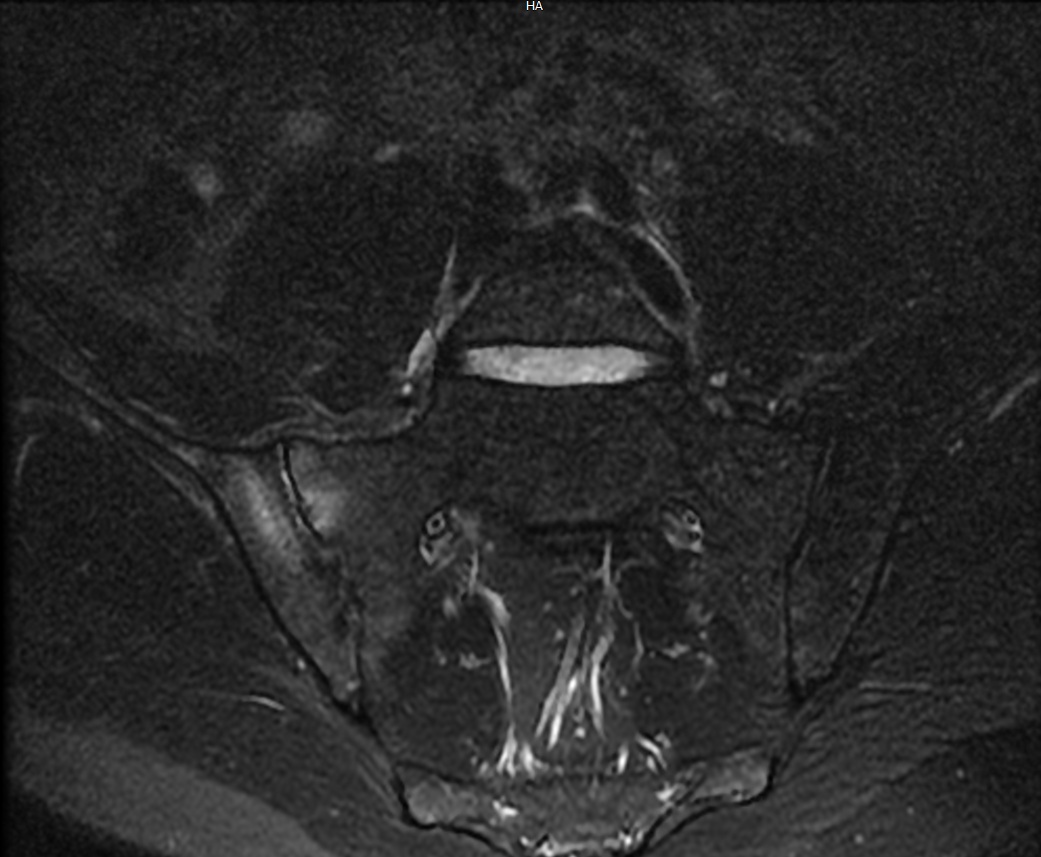

Sacro-iliite droite dans le cadre d'une spondyloarthrite axiale